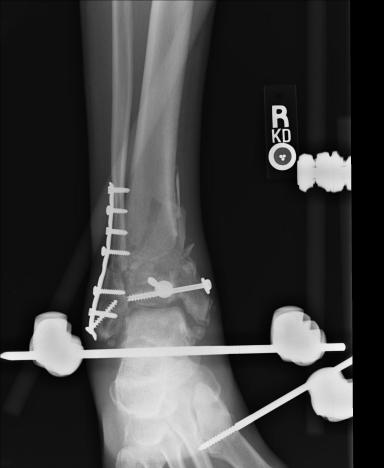

Postoperative (14th) images of left ankle

The image(s) displayed here were created following Liam's 14th surgery which was performed by Dr. Saunders. It was thought that the bones

in the ankle had fused, but during surgery it was discovered that the ankle was a total non-union. The halo frame was removed and 3 anchors were

placed on the tibia. Also added to the ankle was all available Medtronic Infuse material (rhBMP). One image may provide proof that Dr. Saunders

is possessed. ;-) The first set of x-ray shots were taken 3 weeks after the 14th surgery. The 3 new claw anchors are visible as seen through

the cast. Excess bone debris was also removed. Some of the photos had to be taking with the cell phone since the main camera failed. The last

x-rays show that some of the screws in the claw anchors are backing their way out of the leg. The next phone photos show that a screw from a

claw anchor was actually sticking out of the leg and could easily be removed (by hand) by the doctor. The very last photo is of the leg wrapped

in a black cast. Black was used to signify the loss that was soon going to occur. :-(